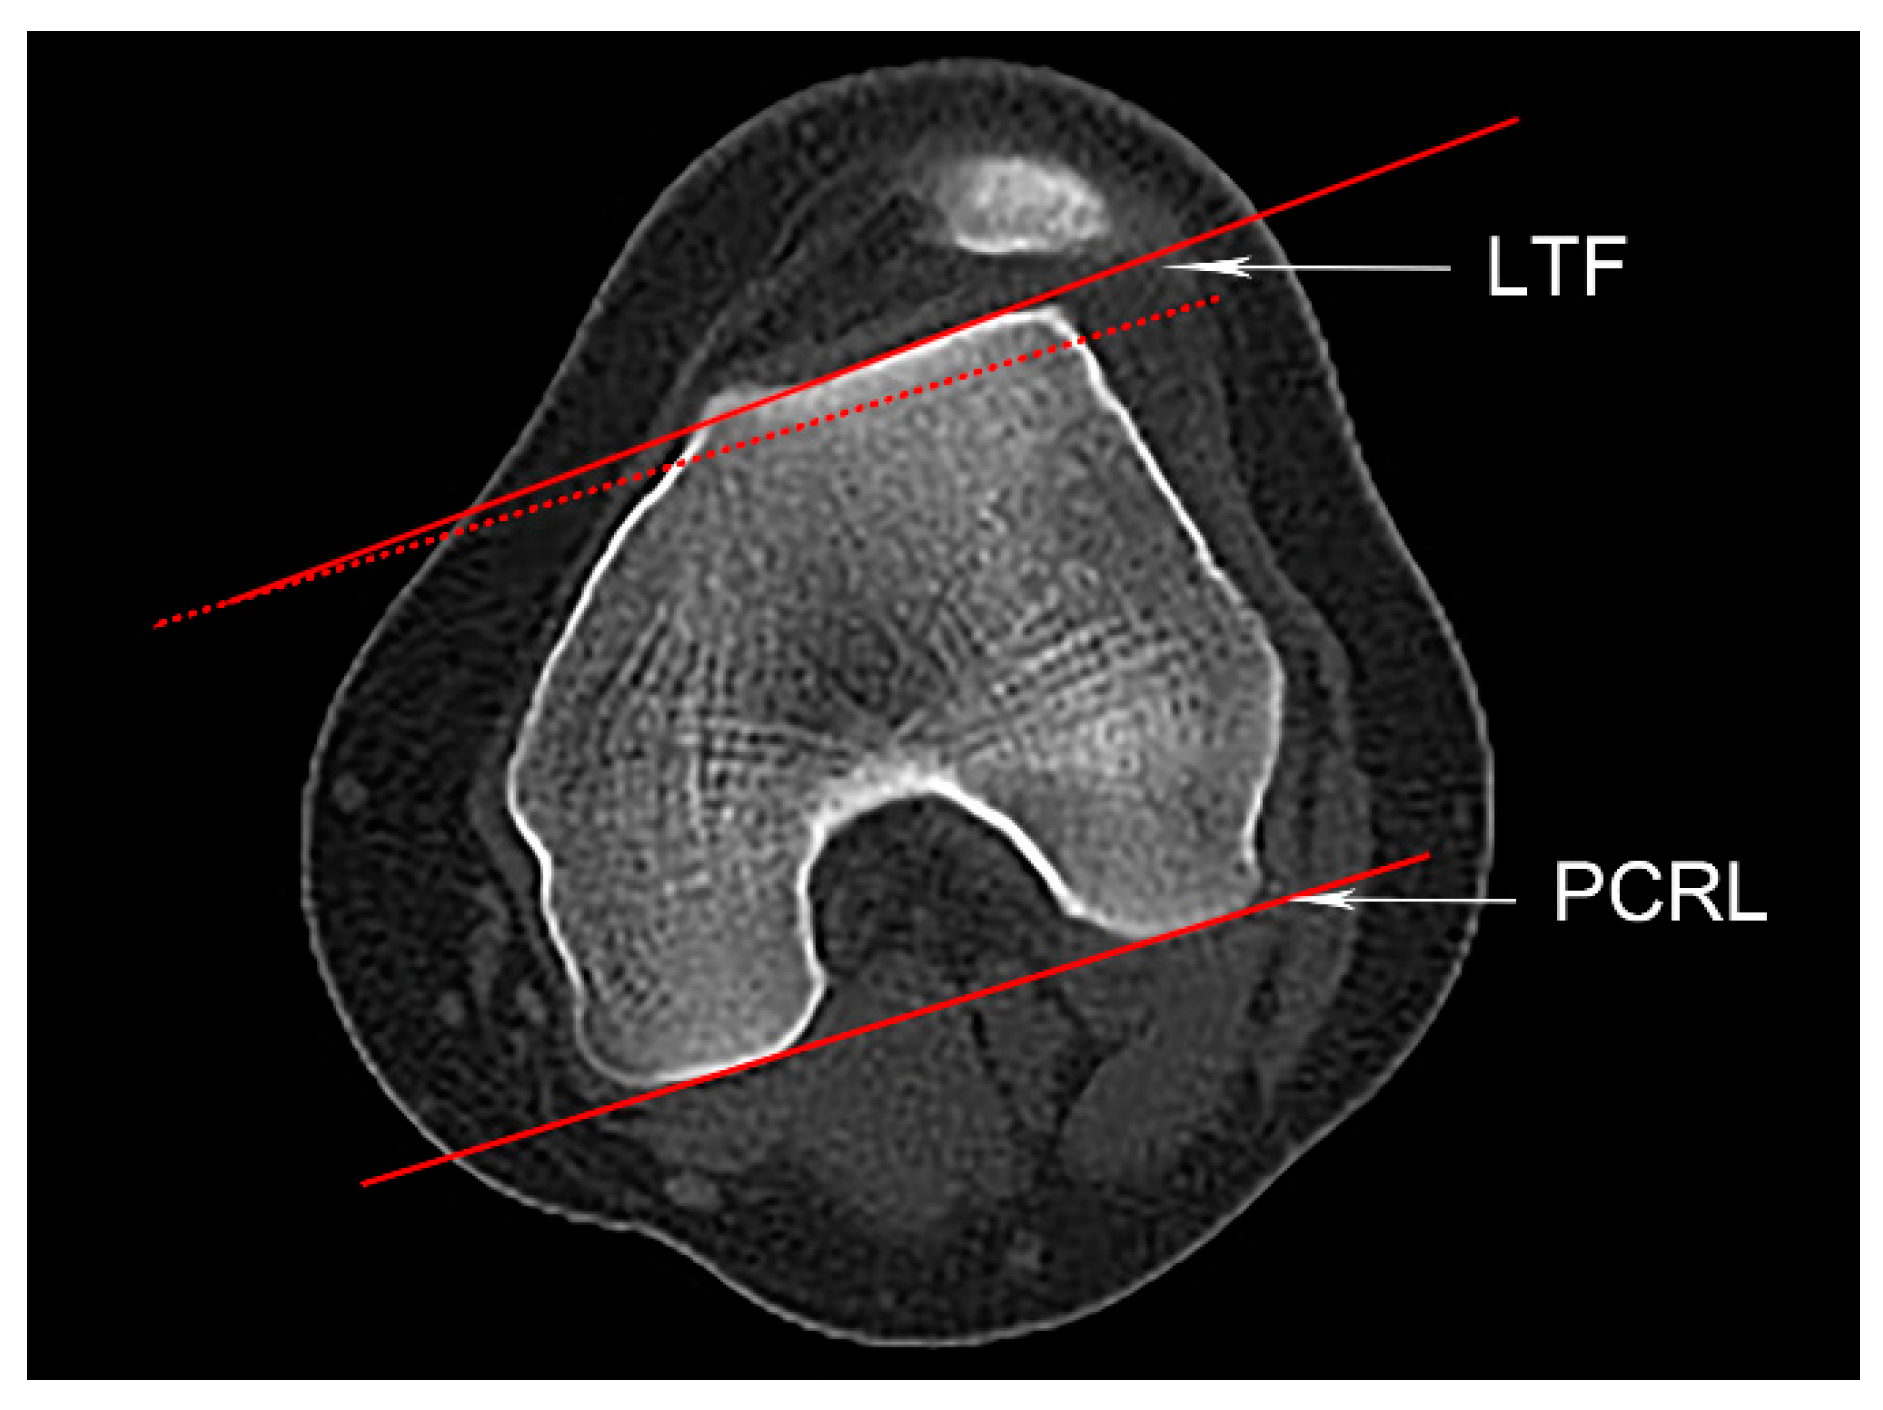

Trochlear dysplasia includes four subtypes identified by axial CT slice according to the Dejour classification [15]. Type A (mild) shows a relatively shallow trochlea; type B shows a flat or convex trochlea; type C has a convex medial trochlear wall and asymmetric facets; type D (severe) presents asymmetric trochlear facets with a cliff. The LTI was a reliable parameter for objectively evaluating trochlear dysplasia, with a value of less than 11° indicating trochlear dysplasia [16]. It is the angle formed between the PCRL and the tangent line of the lateral trochlear facet (Figure 2).

Figure 2.

Lateral trochlea inclination (LTI). An axial slice showing an intact “Roman Arch” and the femoral condyles. The posterior condylar reference line (PCRL), its parallel line (the red dotted line), and a tangent line of the lateral trochlear facet (LTF) are shown. The LTI is defined as the angle between the PCRL and the LTF.